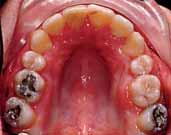

The oral hygiene was fair but needed improvement prior to orthodontic treatment. All teeth from the left permanent second molar to the right have erupted in both the upper and lower arches. The patient had carious lesions in both upper first molars, upper left second molar and lower left first molar. The maxillary arch was spaced with a midline diastema. Furthermore, there was mild lower labial segment crowding (4mm). The incisor relationship was Class II division 1, the overjet was 12 mm whereas the overbite was increased and complete to the palate

and causing trauma to the palatal mucosa. The centrelines were coincident and the buccal segment relationship was 1/2 unit Class II on both sides (Figure 2).

The treatment of the case was planned in stages. Stage one consistedof improving the oral hygiene of the patient and management of all carious lesions and assesses the compliance and attitude of the patient towards orthodontic treatment. The next stage involved the reduction of the overbite. The patient presented with a deep overbite that was causing damage to the palatal mucosa (Figure 2). This was achieved with an anterior bite plane removable appliance and bonding of the lower arch. This appliance will free the occlusion of the buccal segment teeth and if worn consistently, will “passively” limit further eruption of the incisors but allow the lower premolars to erupt, thus reduce the increased overbite (Figure 5).